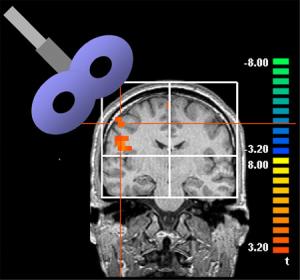

A técnica, chamada de Estimulação Transcranial Magnética, se utiliza de uma bobina metálica que emite pulsos eletromagnéticos na cabeça do paciente para excitar o tecido cerebral. Ela já vinha sendo usada para tratar pessoas com enxaquecas, que tiveram derrames, pacientes com mal de Parkinson e depressão. Entretanto, essa é a primeira vez que é usada em alguém em coma.

Os campos magnéticos enviados pela bobina ao cérebro têm o poder de excitar ou inibir as células, o que pode fazer com que elas se comuniquem com maior facilidade ou com maior dificuldade.

O paciente descrito teve as células do córtex pré-frontal do lado direito do cérebro estimuladas. Essa área é ligada ao tronco cerebral, que manda sinais para o resto do corpo avisando que ele deve ficar em alerta.